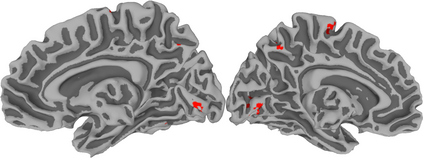

Functional Magnetic Resonance Imaging (fMRI) maps cerebral activation in response to stimuli but this activation is often difficult to detect, especially in low-signal contexts and single-subject studies. Accurate activation detection can be guided by the fact that very few voxels are, in reality, truly activated and that these voxels are spatially localized, but it is challenging to incorporate both these facts. We address these twin challenges to single-subject and low-signal fMRI by developing a computationally feasible and methodologically sound model-based approach, implemented in the R package MixfMRI, that bounds the a priori expected proportion of activated voxels while also incorporating spatial context. An added benefit of our methodology is the ability to distinguish voxels and regions having different intensities of activation. Our suggested approach is evaluated in realistic two- and three-dimensional simulation experiments as well as on multiple datasets. Finally, the value of our suggested approach in low-signal and single-subject fMRI studies is illustrated on a sports imagination experiment that is often used to detect awareness and improve treatment in patients in persistent vegetative state (PVS). Our ability to reliably distinguish activation in this experiment potentially opens the door to the adoption of fMRI as a clinical tool for the improved treatment and therapy of PVS survivors and other patients.